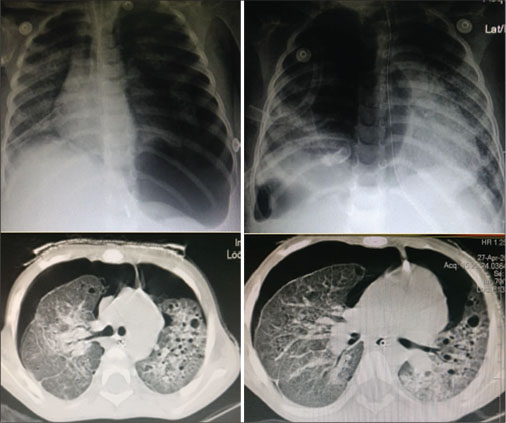

In the PICU, she was intubated and started on mechanical ventilation and supportive care. She developed bilateral pneumothoraces requiring intercostal drainage tubes. Following extubation considering the nonresolution of symptoms and unusual occurrence of pneumothorax in a child with miliary tuberculosis, a chest computed tomography (CT) was performed [Figure 1]. This revealed multiple nodules and thin-walled cysts all over both lungs. Many cysts were subpleural. This characteristic radiological picture suggested LCH. Closed lung biopsy was attempted, but the biopsy findings were noncontributory. The child continued to have respiratory distress and oxygen requirement with bilateral extensive coarse crepitations. She had multiple episodes of worsening of respiratory distress with increased oxygen requirement due to repeated episodes of fresh pneumothoraces on both sides. Besides her respiratory symptoms and signs, she had no other findings to suggest LCH of other organs. Evaluation of blood counts, skeletal survey, and liver function tests was all normal. Considering the typical radiological findings of LCH, the plan was to give her a trial of chemotherapy as per the LCH III protocol (Vinblastine and prednisolone). She was also started on intensive nutritional supplementation. After 2 weeks of therapy, her general condition had not significantly improved and she continued to have episodes of pneumothorax requiring new intercostal draining tubes. In consultation with pulmonary medicine, therapeutic pleurodesis was planned with povidone-iodine. She was given two doses of povidone-iodine on both sides and tolerated the treatment well. After 4 weeks of chemotherapy, her oxygen requirement had reduced and intercostal drain tubes were removed. She tolerated this well with no recurrence of pneumothorax. Her interval assessment at 6 weeks showed a significant improvement in the lung parenchyma but the persistence of few nodules and cysts [Figure 2]. A second 6-week induction course of chemotherapy was administered followed by maintenance chemotherapy for 6 months. She is currently well with no respiratory signs and symptoms with lung imaging showing no nodules or cysts. She has gained weight and has no active disease on follow-up.

| Figure. 2 X ray and CT chest post chemotherapy and bilateral povidone iodine pleurodesis showing residual cysts but complete resolution of pneumothorax. (Six weeks from diagnosis)